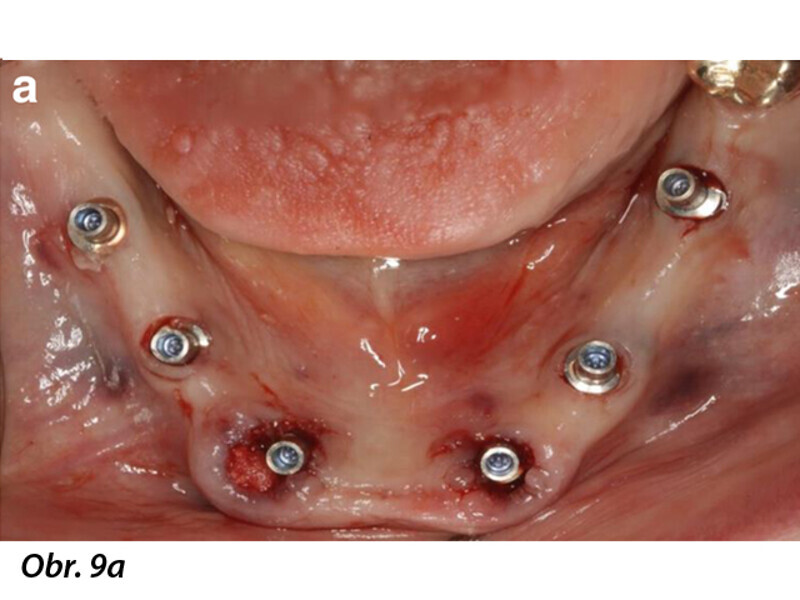

Počítačem asistované, šablonou se řídící okamžité zavedení a zatížení implantátu v dolní čelisti